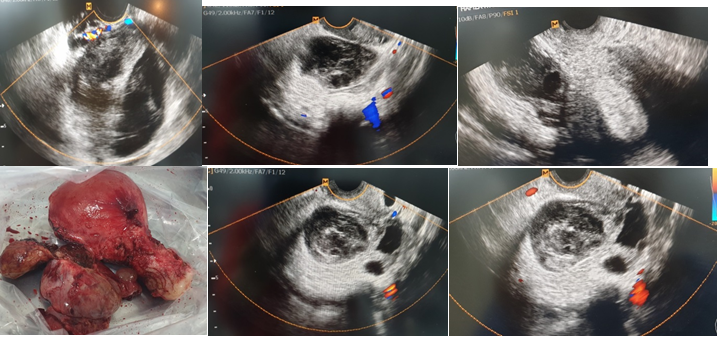

Case 1: A 67-year-old lady (gravida 5, para 3, abortions 2) complained of nausea and lower right abdomen discomfort. The lower abdomen was soft on physical examination, with minor soreness in the right adnexa. Ultrasound examination revealed a slightly enlarged right ovary with normal appearance and Doppler imaging showed inside flow with echogenic side and presence of echogenic cyst. Torsion of the right adnexa with ovarian cyst was discovered during a laparotomy. Hysterectomy and bilateral salpingectomy were done (Figure 1). Histology results were torted ovarian serous cystadenoma with atrophic endometrium.

Figure 1 Vaginal ultrasound pictures demonstrating a big ovary (> 4 cm) with edema and a positive intra-ovary Doppler. An ovarian serous cystadenoma with atrophic endometrium was discovered during surgery.